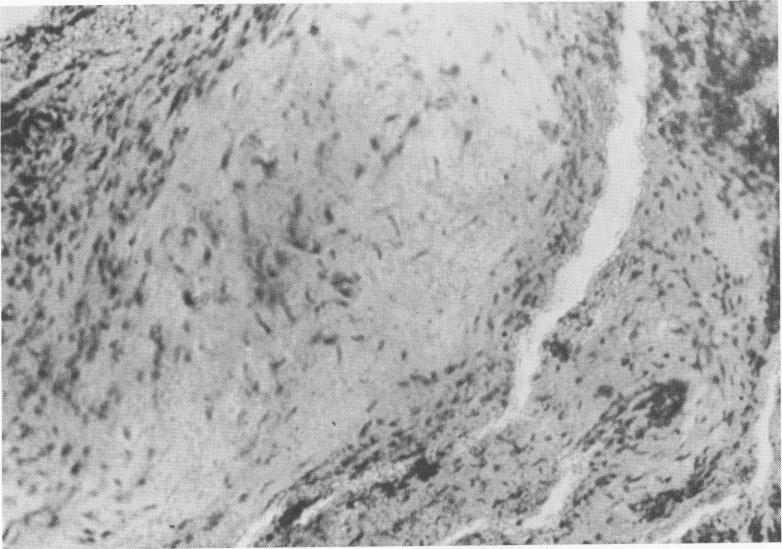

Fig. 4-9. The young connective tissue from around the site has numerous histiocytes. (From Chercheve, R.: Les implants endo-osseux, Paris, 1962, Librairie Maloine.)

2 Connective tissue with numerous histiocytes at Formiggini implant site